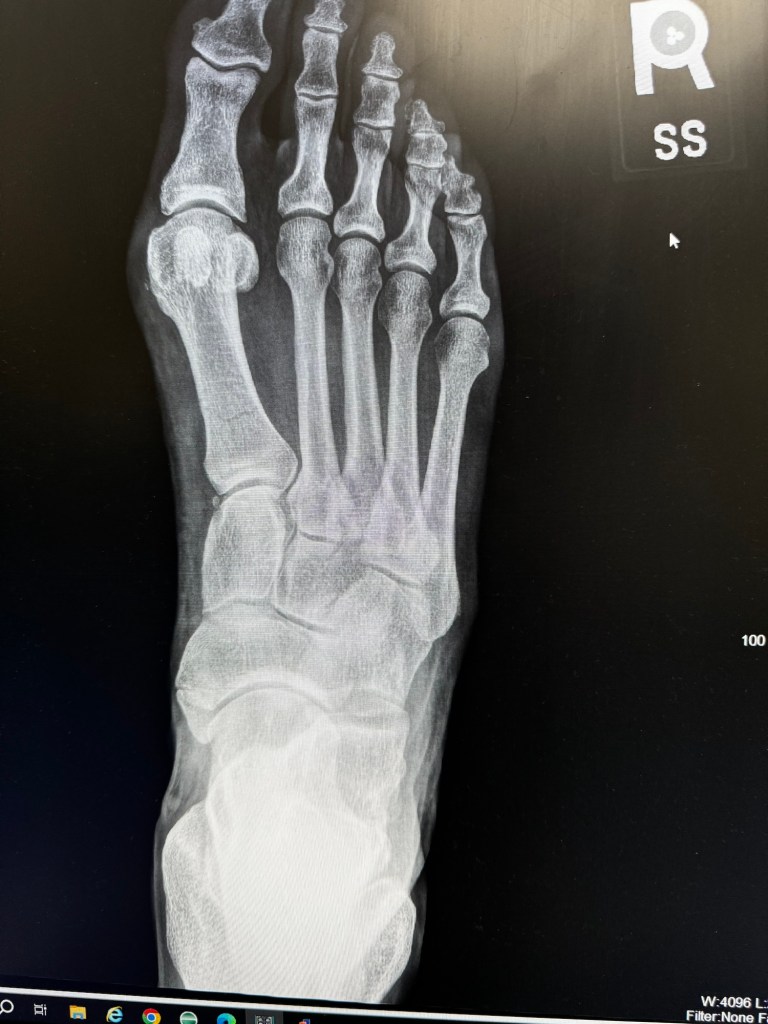

There is a piece at the outer edge that pushes the outside edge back into the middle. It got bent so I wanted to take it off, beat on it with a hammer and decide if it needed anything else. I was working on it with the sickle bar in the upright position and it was slow going. I opted to lower the sickle bar to make it easier to work on. I undid the bar holding it upright then just dropped the bar. There is this chain mechanism that usually catches it. Upon later reflection that chain only engages when the three point hitch is elevated which it was not. I dropped that bar directly on top of my right foot. To say that I may have said a few choice words after a solid howl is an understatement. As soon as I could catch my breath I went on a verbal rampage against the sickle bar. It took about 15 minutes before I could move or feel my toes. Once I could move my toes I was pretty sure I had broken my foot, the pain and swelling were getting localized.

I had called Annmarie, she was still at work, to come get me. I considered driving but it was my right foot and I could not walk. My car is a standard and I was certain I could not drive with my right foot. I made such a raucous that the siding guy hollered out and asked if I needed any help. I yelled back that I had just broken my foot but was fine. He went back to siding. I ended up in the ER, I broke a metatarsal in my right foot. I am on crutches, wearing a boot and am 100% non-weight bearing for the next eight weeks! This totally sucks! Luckily, Mr Rainman is chugging away at the hay. He has another 300 bales done and two more fields cut. There is hope that he can be done with haying by the end of the week. Once the haying is done then the gazebo is the next project. I have a new throttle cable coming for the compactor and once that is installed we can prep the pad for the gazebo.